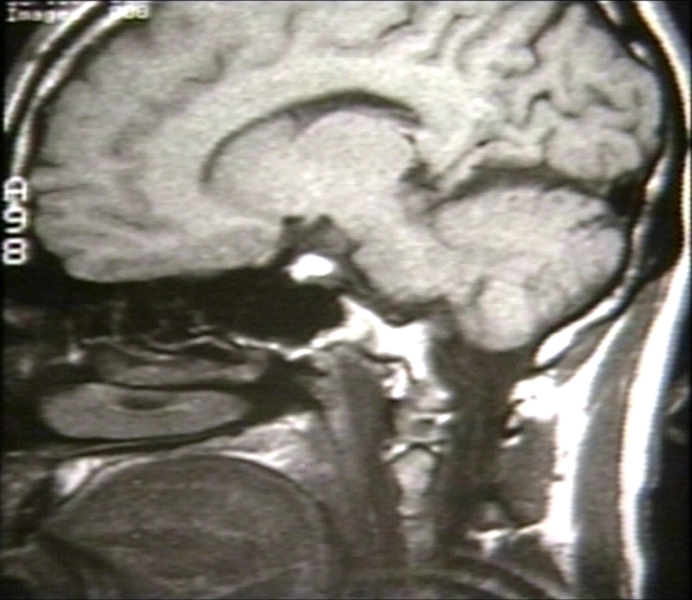

RADIOLOGY: NERVOUS: BRAIN: BRAIN, CT, NORMAL, ANATOMY; 8/12- NINTH IN SERIES (MRI)